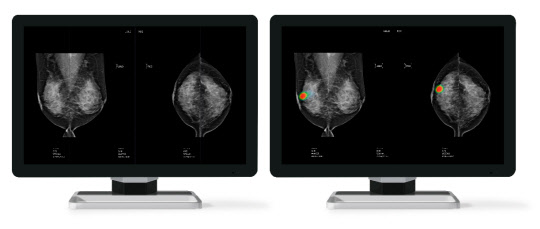

루닛의 유방암 진단 보조 AI 솔루션 '루닛 인사이트 MMG'. 루닛 제공

연구팀은 실제 검진 현장에서 영상의학과 전문의들이 판독한 유방 촬영술 데이터 결과와 루닛의 유방암 진단 보조 AI 솔루션인 '루닛 인사이트 MMG'가 판독한 데이터 결과를 비교 분석해 정확도를 측정한다.